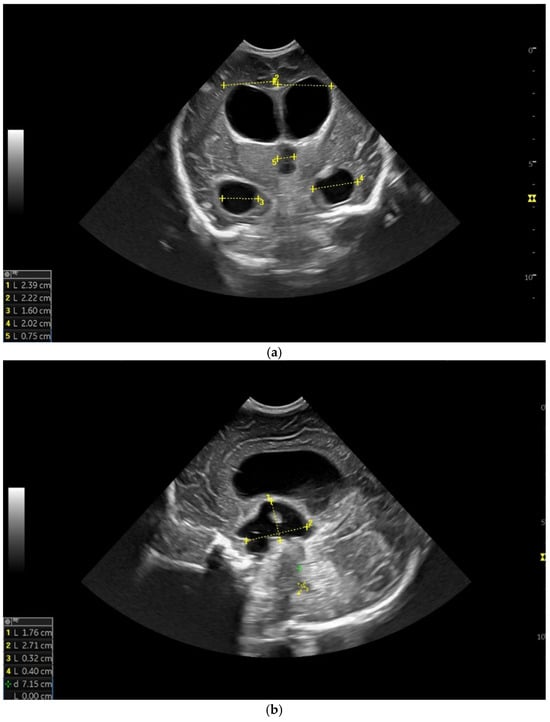

At two minutes of life, with a heart rate of 120 bpm, chest compressions were discontinued, and the patient continued to be ventilated via endotracheal tube. The newborn was then transported while ventilated in an incubator to the neonatal intensive care unit (NICU), where SIMV ventilation was initiated, along with surfactant administration. The day one cranial ultrasound (CUS) showed bilateral periventricular hyperechoic images and enlargement of the lateral ventricles (Figure 1a–d).

Figure 1.

(a) Cranial ultrasound. Day one. Coronal view. D1 and D2—Levine index measurement. D3—cisterna magna measurement (personal image collection). (b) Cranial ultrasound. Day one. Coronal view. Lateral ventricle dilatation. LV—lateral ventricles. PC—plexus choroidus (personal image collection). (c) Cranial ultrasound. Day one. Right lateral ventricle. D1—thalamo-occipital distance measurement. Yellow arrow—parieto-occipital hyperechoic images (personal image collection). (d) Cranial ultrasound. Day one. Left lateral ventricle. D1—thalamo-occipital distance measurement. Yellow arrow—parieto-occipital hyperechoic images (personal image collection). (e) Day three. Cranial ultrasound. Coronal view. Ventricular asymmetry. D1 and D2—Levine index measurement. D3 and D4—anterior horn width measurement. Left ventricular enlargement (personal image collection). (f) Day three. Cranial ultrasound. Coronal view. Ventricular asymmetry (left ventricle larger than right ventricle). Yellow arrows—periventricular hyperechoic images are becoming more visible (personal image collection). (g) Day three. Cranial ultrasound. Coronal view. Linear probe. Ventricular asymmetry (left ventricle larger than right ventricle). LV—lateral ventricle (anterior horns). IHF—interhemispheric fissure. Yellow arrows—hyperechoic images in the thalamic-caudate groove (suggestive of a germinal matrix hemorrhage) (personal image collection). (h,i) Day 13. First LP. Cranial ultrasound. Coronal view. Up (before LP). D1 and D2—Levine index measurement. LV—lateral ventricles (anterior horns). IHF—interhemispheric fissure. Down (after LP). Dimensions of ventricles were reduced after LP. D1 and D2—anterior horn width. LV—lateral ventricles (anterior horns). OH—occipital horn (personal image collection). (j,k) Day 19. Second LP. Cranial ultrasound. Coronal view. Dimensions of ventricles were reduced after LP. Left (before LP). D1 and D2—Levine index measurement. Right (after LP). D1 and D2—Levine index measurement (personal image collection). (l) Day 39. Cranial ultrasound. Coronal view. Yellow arrows—periventricular cystic hyperechoic images—suggesting periventricular leukomalacia (cystic form) (personal image collection). (m) Head circumference-for-age. “X” symbols represent the measurements performed from birth and follow-up examinations. Initially, the head circumference was under the curve (personal image collection) [28].

After 72 h, the patient was extubated. The CUS showed bilateral IVH (grade III Volpe/Papile) (Figure 1e,f).

During the in-stay, two lumbar punctures (LP) were performed (Figure 1h–k).

In evolution, our patient presented bilateral ventricular dilatation and bilateral PVL (cystic form, grade III) (Figure 1l). The neurological assessment established eye contact and the infant could hold its head during the traction maneuver. The passive tone assessment showed the “scarf sign”, with the elbow at the midline bilaterally and a popliteal angle of 90°. The deep tendon reflexes (DTRs) were symmetrical.